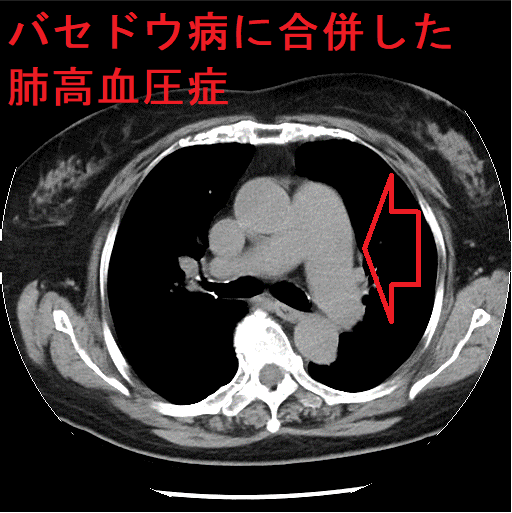

肺高血圧症(慢性血栓塞栓性肺高血圧症)のCT所見は、

- 肺動脈拡大・右心系の拡張

- 斑状のすりガラス影(モザイクパターン)、高吸収域では末梢血管影が目立つ